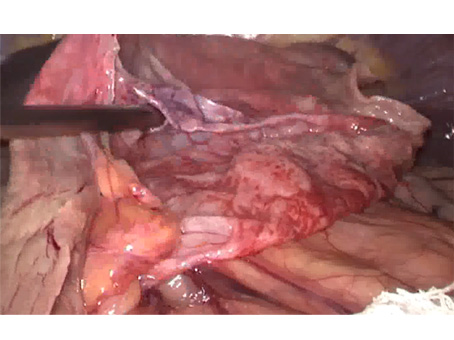

We have state of the art operating theatre with advanced surgical equipments. We have a Karl Storz Spies advanced HD laparoscopy operating system in addition to a 3 chip laparoscopy. We have installed advanced vessel sealing devices like Gen 11 harmonic scalpel, Ligasure from Valley Lab & Argon plasma coagulator. There is a recent addition of Cavitron Ultrasonic Aspirator (CUSA) system into our surgical armamentarium. We have the most recent powered Echelon endo-stapling devices. In addition to all these we have a constant supply of various types of advanced stapling devices for GI surgeries. Our endoscopy machines are having high definition with FICE Technology. Last but not the least we have semi flexible Ureteroscopy for managing common bile duct stones.

CAVITRON ULTRASONIC ASPIRATOR USED FOR LIVER RESECTION

LIVER RESECTION DONE USING CUSA